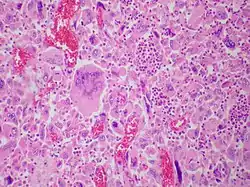

| Pulmonary giant cell carcinoma represents a rare variety of non-small cell lung carcinoma that is characterized by the presence of numerous tumor giant cells and an influx of inflammatory cells that are mostly polymorphonuclear leukocytes admixed with macrophages. The dense oval aggregates of polymorphonuclear leukocytes seen in this image are probably located in the cytoplasm of tumor giant cells (emperiopolesis) that have been sectioned in a plane that does not include their nuclei. | |